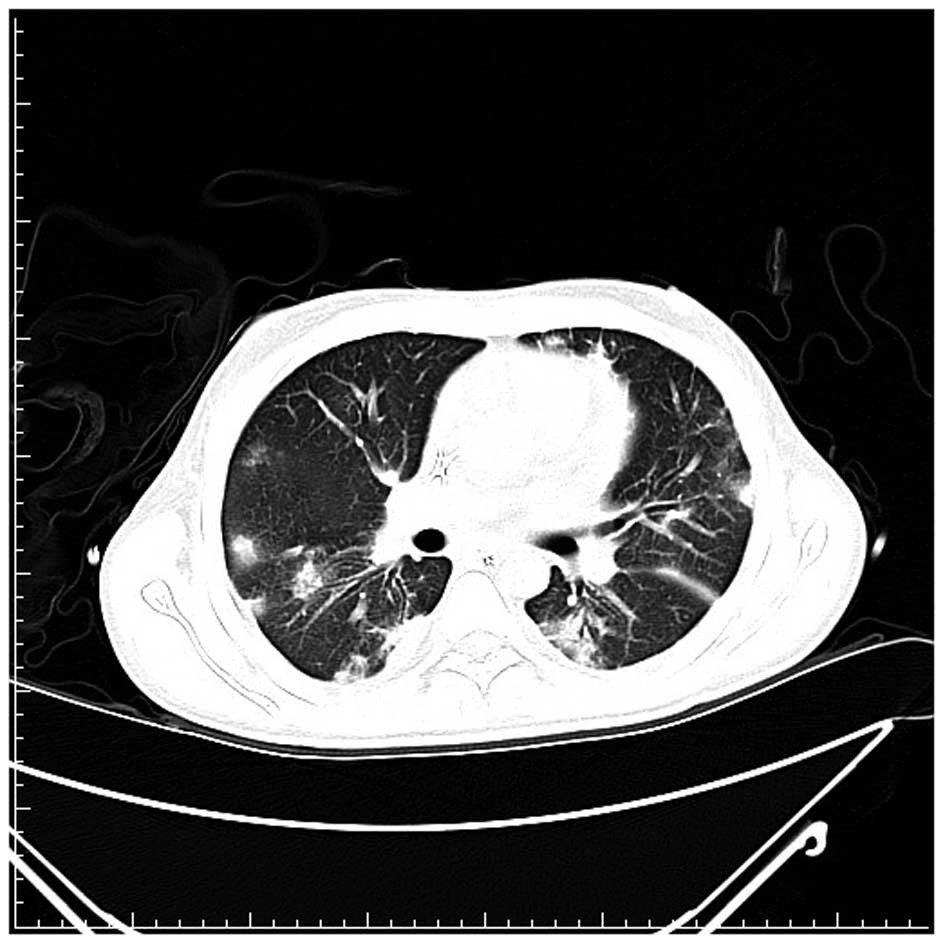

A 20-year-old male was diagnosed with acute lymphoblastic leukemia, precursor B cell type and received induction chemotherapy with TPOG-ALL-2002 VHR protocol (6) with partial remission in the induction course. The patient did not finish the consolidation course due to prolonged neutropenia. Later, the patient relapsed and received chemotherapy with FLAG-IDA (idarubicin, fludarabine, cytarabine and G-CSF) (7). The patient exhibited prolonged febrile neutropenia for more than one month during the initial course of chemotherapy, but exhibited rapid relapse again, soon following neutropenia recovery. In the second course of treatment, the patient received 400 mg oral fluconazole daily as an antifungal prophylaxis. The febrile neutropenia was found two days later. Antibiotic treatment with imipenem/cilastatin (500 mg, i.v., every 6 h), vancomycin (1,000 mg, i.v., every 12 h) and micafungin (100 mg, i.v., daily) was then administrated. After four days, multiple skin lesions, starting from the legs and spreading to the face and upper extremities were identified. The lesions exhibited necrotic centers surrounded by spreading erythema (Fig. 1). The lesions worsened and the antifungal treatment was replaced with caspofungin (100 mg, i.v., daily). A biopsy of the skin lesions showed the presence of hyphae occupying the vascular space. The Gomori methanamine silver and periodic acid-Schiff stains were positive. The histopathological diagnosis was angioinvasive aspergillosis and treatment with voriconazole (200 mg, i.v., every 12 h) was initiated in addition to caspofungin with poor response. The amphotericin B was not administered due to ethical issues (the patient and family refused further aggressive treatment owing to refractory acute lymphoblastic leukemia with poor therapeutic response). A high-resolution computed tomography scan of the lungs found multiple speculated and round consolidative densities in the lungs (Fig. 2). After three weeks, the sputum and skin tissue cultures finally demonstrated Fusarium spp. colonization (Fig. 3). The patient succumbed to the disease two months later. Written consent was provided from the patient’s family.

Figure 2

Radiological observations may indicate non-specific infiltrates to nodular and/or cavity formation.

As with the case of Aspergillus, the radiological observations of pulmonary Fusarium infection are non-specific, including non-specific infiltrates to nodular and/or cavity formation, depending on the timing of the examination (9). The prognosis is considerably worse in patient pulmonary infiltrates (10).